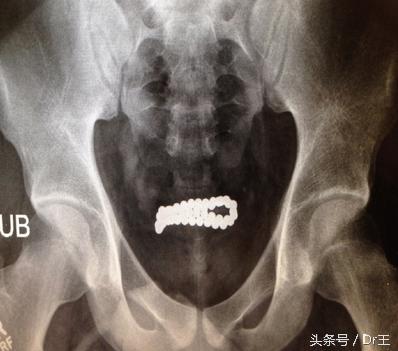

尿道塞异物的案例屡见不鲜,而塞进尿道的物品更是千奇百怪,最常见的当属原子笔、发夹、筷子等,外型细小呈条索状的异物,还有钱币、橡皮擦、口红、回形针等,甚至有人把蛇硬生生塞进尿道。

曾收治一名40多岁男性,只要心情不好就往尿道塞原子笔芯,但又直又光滑的笔芯常滑进膀胱。他羞于就医,但却戒不掉癖好,每次都直到笔芯再也塞不进尿道才就医,前前后后就医十多次,有时能用内视镜夹出,若较为严重则要开刀才能取出。

若塞入的异物滑入膀胱,患者又认为「眼不见为净」,异物长期在膀胱内,可能形成膀胱结石,造成排尿困难或尿滞留,或引起膀胱病变、反复性尿路感染、结石,而影响肾脏功能。